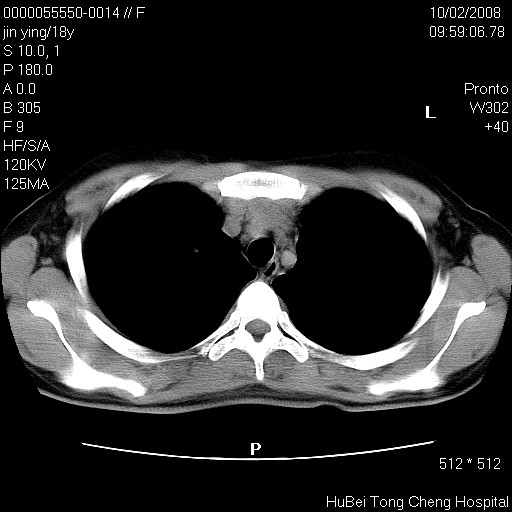

患者 女,18y。发热十余天,伴咳嗽。pe:t39⒈℃,bp 110/80mmhg,p 86次/min。神清,精神欠佳。双肺可闻及少许湿罗音。既往史不详。

临床诊断:肺部感染?

胸部ct轴位平扫(层厚10mm,螺距1.5,重建间隔10mm),图像如下: